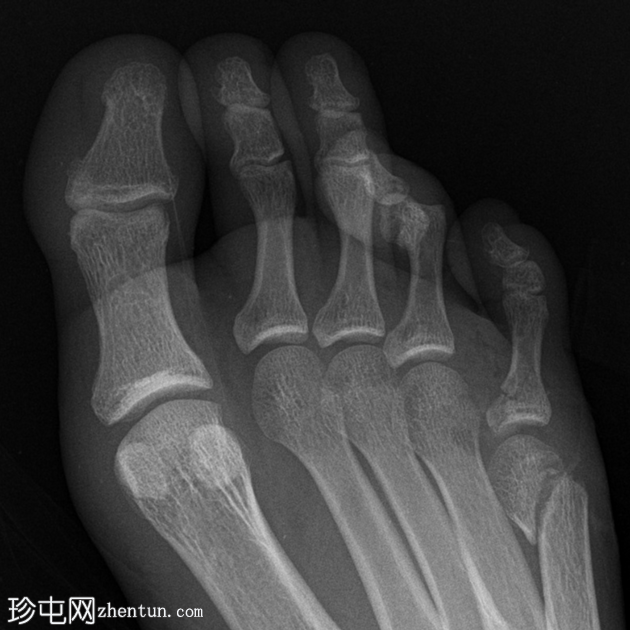

3.png

侧位

跟骨关节内骨折。

如果初始影像检查未能清晰显示关节内骨折延伸情况,则应评估Böhler角和Gissane角。本例中,Böhler角减小,Gissane角增大。这两个发现均证实了关节内跟骨骨折。